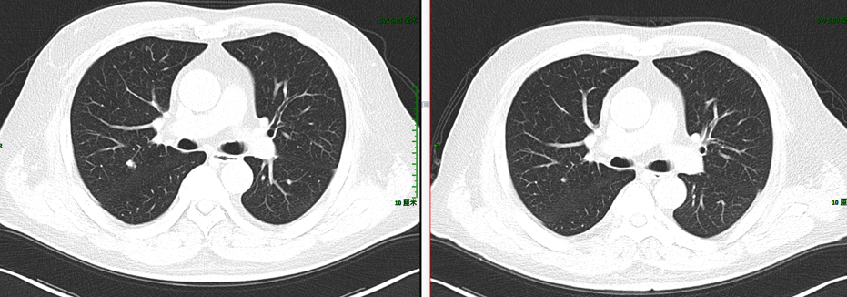

二线治疗:FOLFIRI+贝伐珠单抗

【贝伐珠单抗+FOLFIRI】2018-8-7 我院PET-CT提示直肠癌术后,吻合口FDG代谢未见异常,肝右叶转移瘤切除术后,脂肪肝,残余肝右后叶下段包膜下结节样FDG代谢异常增高(SUVmax 9.9),较前片新增,考虑肿瘤转移可能性大,双肺多发微小斑点、结节影,其中右肺上叶前段、后段两枚小结节(较大者直径约5mm,SUVmax 1.3)较前片新增,考虑为转移瘤可能。

2018-8-11 至 2018-10-11 日予以二线第1-12周期FOLFIRI方案联合贝伐珠单抗靶向治疗,4,8,12疗程评估后稳定。

2019-5-10 至 2020-2 予以维持治疗,具体:贝伐珠单抗 + 卡培他滨,Q21d,PFS1=16m。